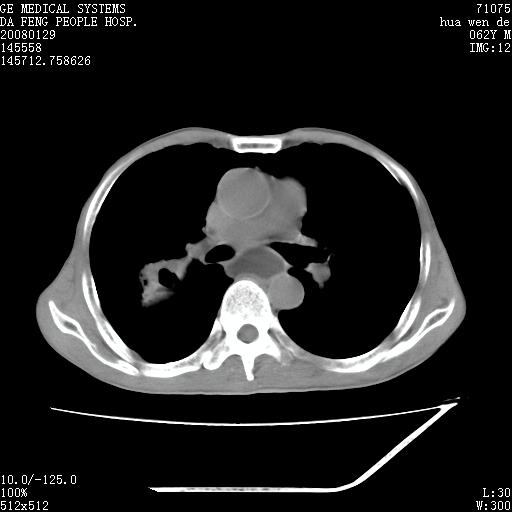

男性,67岁。作肺部检查时发现

理由:1、右上肺内病灶,空洞形成,有液平。

2、肺内多处炎症。

3、前段肺内炎症,支气管引流通畅,与肿块无关系。

1.整个食管扩张,未见明显占位性病变,贲门区亦未见明显占位病变,考虑:贲门失驰缓症;

2.右上肺病变边缘可见毛刺,囊壁厚度不均匀,周围境界较清楚,未见炎性渗出性影,右上肺外带可见片状影,边缘不清,考虑:肺癌伴空洞形成、右上肺炎。

食管全程扩张,壁均匀不厚,喷门失弛缓症

右上肺空洞可见液平,临近肺野磨玻璃密度,考虑1.结核2.脓肿